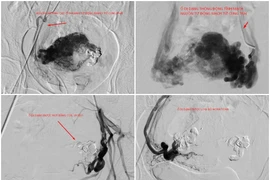

Nút mạch điều trị chảy máu tử cung do thông động tĩnh mạch hiếm gặp

Phụ nữ khi có triệu chứng ra máu âm đạo không đúng kỳ kinh, hay kéo dài bất thường, cần khám sớm để ngăn ngừa nguy cơ xuất huyết nặng, bảo vệ sức khỏe sinh sản.

Ra máu âm đạo ồ ạt do bất thường mạch máu tử cung hiếm gặp

Bất thường nối thông động tĩnh mạch trong cơ tử cung rất hiếm gặp, có thể gây ra tình trạng xuất huyết ồ ạt, kéo dài, đe dọa tính mạng người bệnh.

Bảo tồn tử cung cho người phụ nữ 35 tuổi bị bệnh lý mạch máu hiếm gặp

Bệnh viện Gia Đình (Đà Nẵng) vừa cứu sống nữ bệnh nhân 35 tuổi bị xuất huyết âm đạo nghiêm trọng do thông động tĩnh mạch tử cung - bệnh lý mạch máu hiếm gặp.